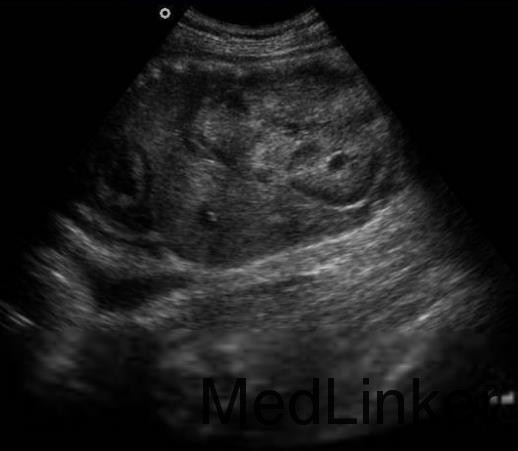

查体:眼睑及双下肢轻度水肿,咽部轻度充血。 辅查:尿蛋白强阳性(+++);24 h 尿蛋白4.87 g;血清清蛋白20.5g/L,血清总胆固醇10.28mmol/L,三酰甘油1.87 mmol/L;活化部分凝血酶原时间46.6 s;纤维蛋白原7.53g/L;IgG3.13 g/L,IgA 1.65 g/L, IgM 1.05 g/L, 补体C3 1.55 g/L,C4 0.35 g/L;双肾B 超:形态正常,皮质回声增强,皮髓分界欠清晰,双肾扫见多个液暗区;腹部CT 平扫:双肾可见多发大小不等类圆形病灶,呈水样均匀低密度,边界清晰。清洁中段尿培养:大肠埃希氏菌,菌落计数:2000 CFU/ml。

诊断:多囊肾,肾病综合征。 治疗:给予激素(泼尼松60mg,每天1 次),辅以低分子肝素钠、双嘧达膜抗凝,辛伐他汀降脂,抗感染及保肾治疗。